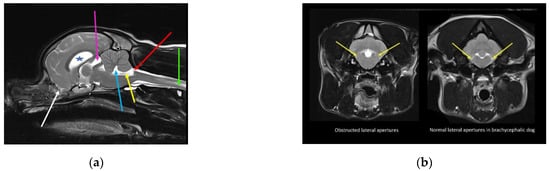

Figure 4.

MRI and CT of a two-year-old female Chihuahua with hydrocephalus, quadrigeminal cistern expansion, and syringomyelia. (a) T2-weighted midsagittal brain and cervicothoracic spine. Yellow star, dilated lateral ventricle; green star, dilated third ventricle; blue star, quadrigeminal cistern expansion with compression of the cerebellum, which is herniated into the spinal canal. White arrow, craniocervical junction abnormality with cervical flexure, angulation of the odontoid peg, and compression of the craniospinal junction. Red arrow, developing cervicothoracic syrinx. (b) Mid-sagittal reformatted CT of the skull and cranial cervical spine. White arrow, craniocervical junction abnormality with cervical flexure, angulation of the odontoid peg, and compression of the craniospinal junction (images created by C. Rusbridge and S.P. Knowler).